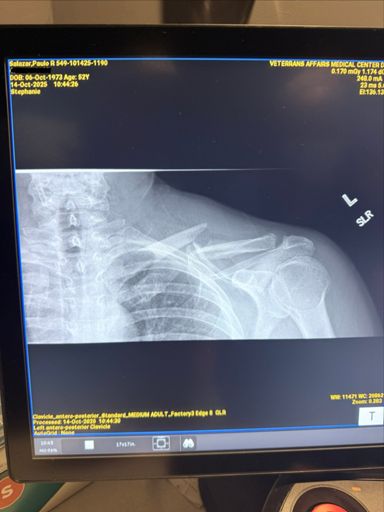

Ranger down! Collar bone is broken. Going to the ER. Cycling season is over for me this year.